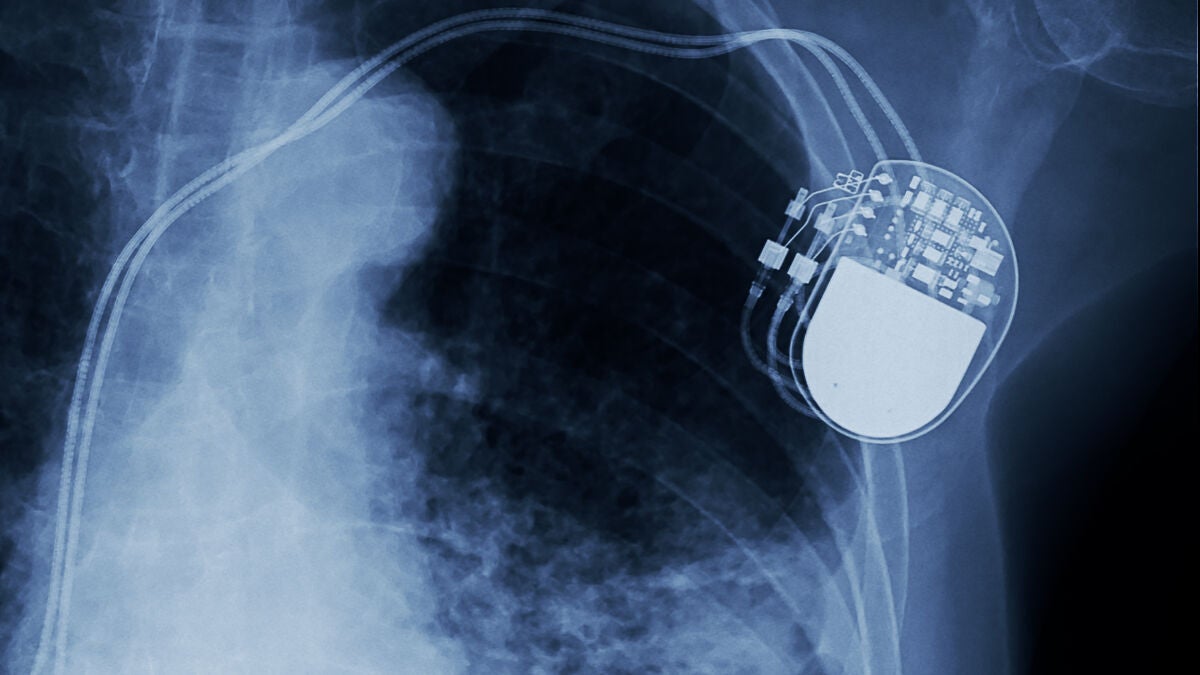

Inventan un marcapasos ultrafino y mínimamente invasivo controlado por luz

La creación de este nuevo marcapasos poco invasivo podría ayudar a reducir las complicaciones en la cirugía cardíaca.

Un equipo de investigadores de la Universidad de Chicago (EstadosUnidos) ha desarrollado un marcapasos inalámbrico, alimentado por luz, que puede implantarse para regular la actividad cardiovascular o neuronal del cuerpo. Las membranas ligeras, más delgadas que un cabello humano, se pueden insertar con cirugía mínimamente invasiva y no contienen partes móviles.